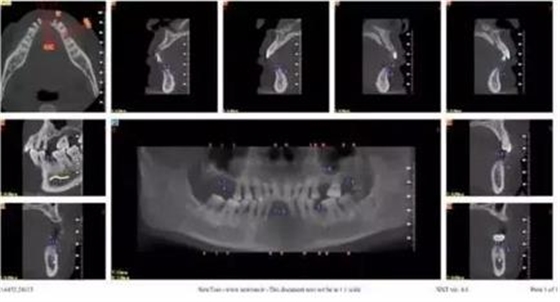

拔牙前CT截圖

通過3shape trios口內(nèi)掃描儀掃描數(shù)據(jù)。

利用3shape導(dǎo)板軟件虛擬排牙

以修復(fù)為導(dǎo)向規(guī)劃植體

牙支持式導(dǎo)板生成

通過3Shape Dental System軟件同期設(shè)計(jì)臨時(shí)冠